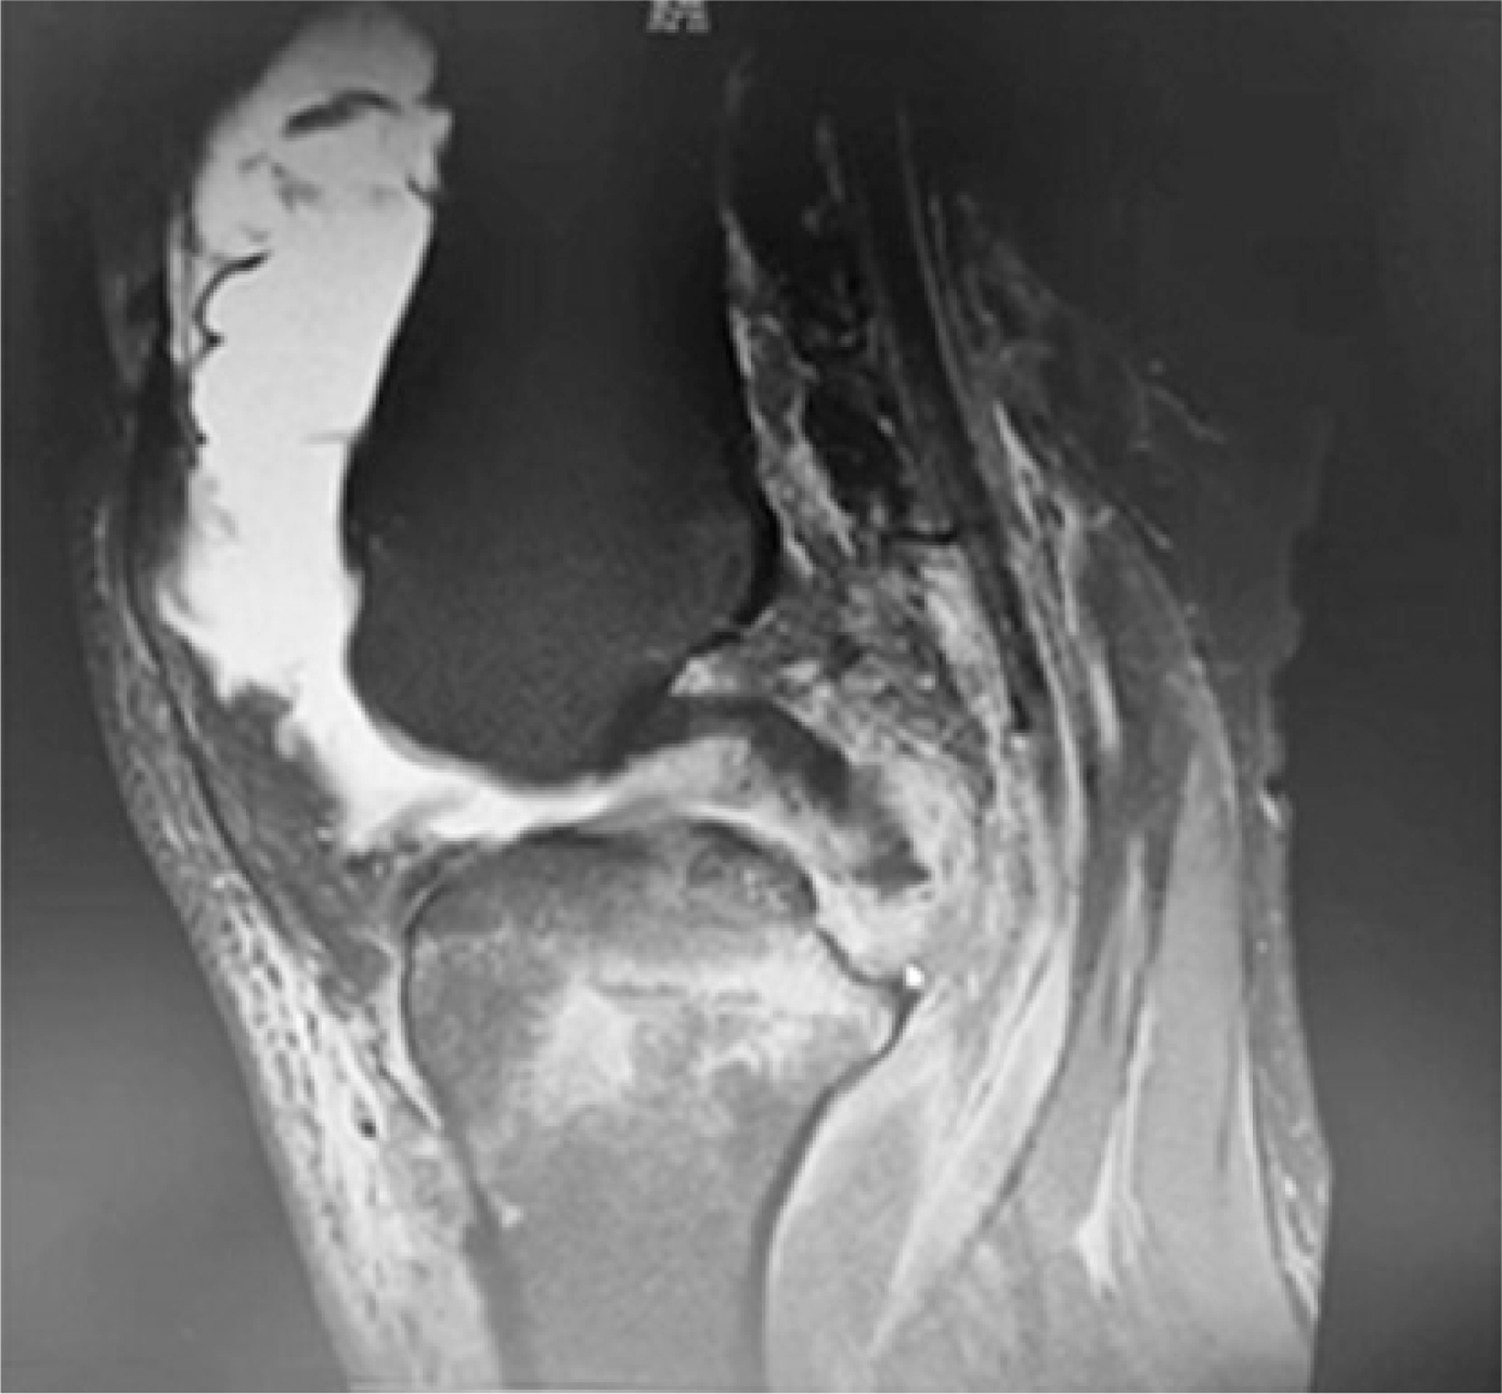

The study group underwent autologous hamstring tendon single-bundle reconstruction combined with braided thread treatment. It adopts double Endo-Button technology and uses Ethicon thread to knit with a flat knot (Figure 1). The technique is as follows: Braid to the desired length, wrap and suture the tendon around the braided wire (the total diameter of the graft is 9 mm) (Figure 2). MRI taken intraoperatively as well as pre- and postoperatively are shown in Figures 3–5.